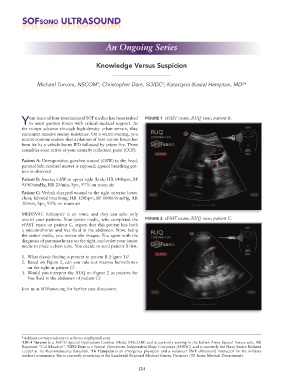

our team of four international SOF medics has been tasked FIGURE 1 eFAST exam, RUQ view, patient B.

Patient B: Awake; GSW to upper right flank; HR 140bpm, BP

95/60mmHg, RR 25/min, Spo 97% on room air

MEDEVAC helicopter is en route and they can take only

one of your patients. Your junior medic, who completed the FIGURE 2 eFAST exam, RUQ view, patient C.

eFAST exam on patient C, argues that this patient has both

a pneumothorax and free fluid in the abdomen. Now, being

the senior medic, you review the images. You agree with the

diagnosis of pneumothorax on the right, and order your junior

medic to place a chest tube. You decide to send patient B first.

1. What classic finding is present in patient B (Figure 1)?

2. Based on Figure 2, can you rule out massive hemothorax

on the right in patient C?

3. Would you interpret the RUQ on Figure 2 as positive for

free fluid in the abdomen of patient C?